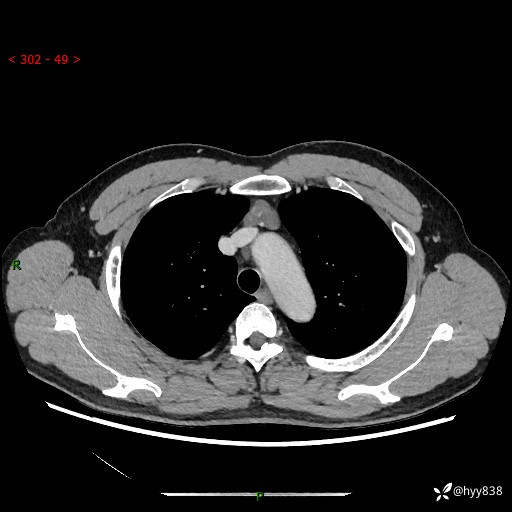

患者性别:女

患者年龄:49岁

简要病史:跟骨骨折,常规CT发现纵隔占位

辅助检查:CT

临床诊断:纵隔占位

增强(动脉期+静脉期)